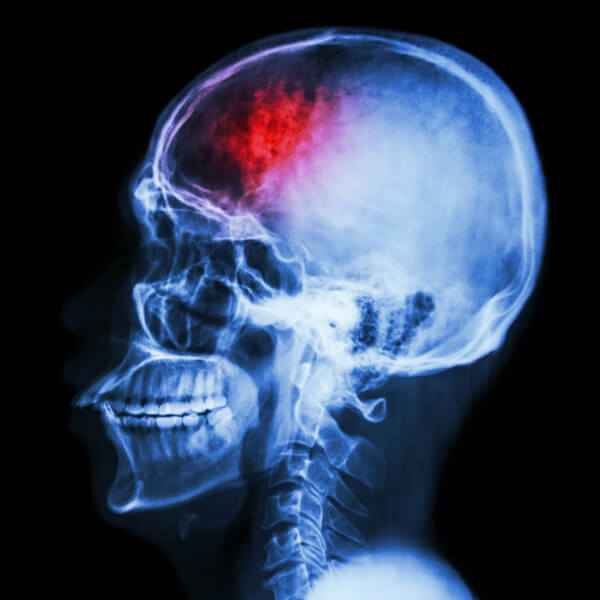

Curso de Traumatismo cráneo-encefálico. Enfoque multidisciplinar

El traumatismo cráneo-encefálico es la segunda causa de mortalidad por causas neurológicas, tras las enfermedades cerebrovasculares. De hecho, en Estados Unidos, por ejemplo, ocurren, en tan solo un año, 10 millones de casos, de los que el 2’% llevan asociados lesiones cerebrales. En España, en concreto, la incidencia se sitúa en 200 casos nuevos por 100.000 habitantes, de los cuales el 80% son considerados graves, un 10% moderados y el otro 10% restante leve.